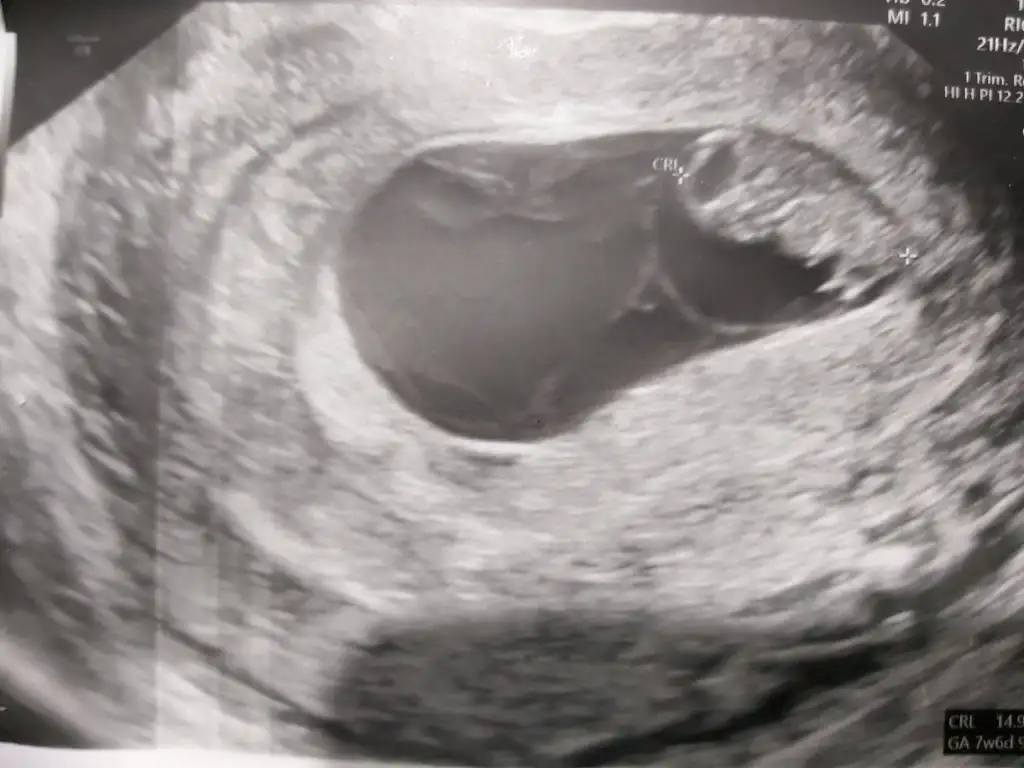

Kızlar benimki bu teoriye göre kız mi oluyor 7 haftalık bu görüntü şuan 11 iz vajinal ultrason buda.